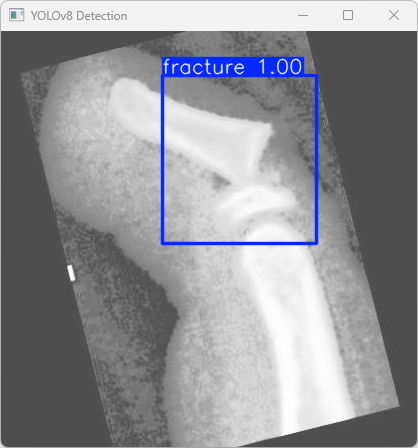

执行imgTest.py代码后,会将执行的结果直接标注在图片上,结果如下:

这段输出是基于YOLOv8模型对图片“imagetest.jpg”进行检测的结果,具体内容如下:

图像信息:

(1)处理的图像路径为:TestFiles/imagetest.jpg。

(2)图像尺寸为 640×640 像素。

检测结果:

(1)模型检测到图片中有1个骨折 (fracture)。

(2)每张图片的推理时间4.0毫秒。

处理速度:

(1)预处理时间:4.4毫秒,用于准备输入图像数据。

(2)推理时间:4.0毫秒,用于模型推理,即检测骨折的时间。

(3)后处理时间:48.7毫秒,用于将推理结果转换为可视化或保存的结果。

显示了YOLOv8模型成功地检测到了一张测试图像中的一个骨折,检测速度较快,且结果已保存到指定的文件夹中。